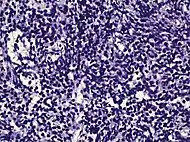

| Subdiagnosis | Relative incidence | Image | Microscopic characteristics | Immunohistochemistry | Gleason scoring | ||

| Acinar adenocarcinoma - 93%[2] | Adenocarcinoma (not otherwise specified/ conventional/ usual acinar)[3] |

77%[notes 2] | 54%[notes 2] | ![]() |

These constitute 93% of prostate cancers.[2]